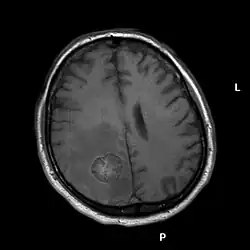

Kernspintomographie

Die Kernspintomographie weist bei besserer Weichteildifferenzierung, insbesondere nach Gabe von Gadolinium als Kontrastmittel, eine deutlich höhere Sensitivität auf und ist somit geeigneter für die Suche nach Hirnmetastasen. So ist im Vergleich zur CT-Untersuchung die Rate der Patienten mit im MRT nachgewiesenen Hirnmetastasen mehr als doppelt so hoch.[8] Das gilt besonders für sehr kleine Befunde und Metastasen im Bereich der hinteren Schädelgrube. Die Kernspintomographie kann zur Abgrenzung gegen Hirnabszesse oder andere möglicherweise ähnlich imponierende Läsionen um eine Kernspinresonanzspektroskopie ergänzt werden.[9]